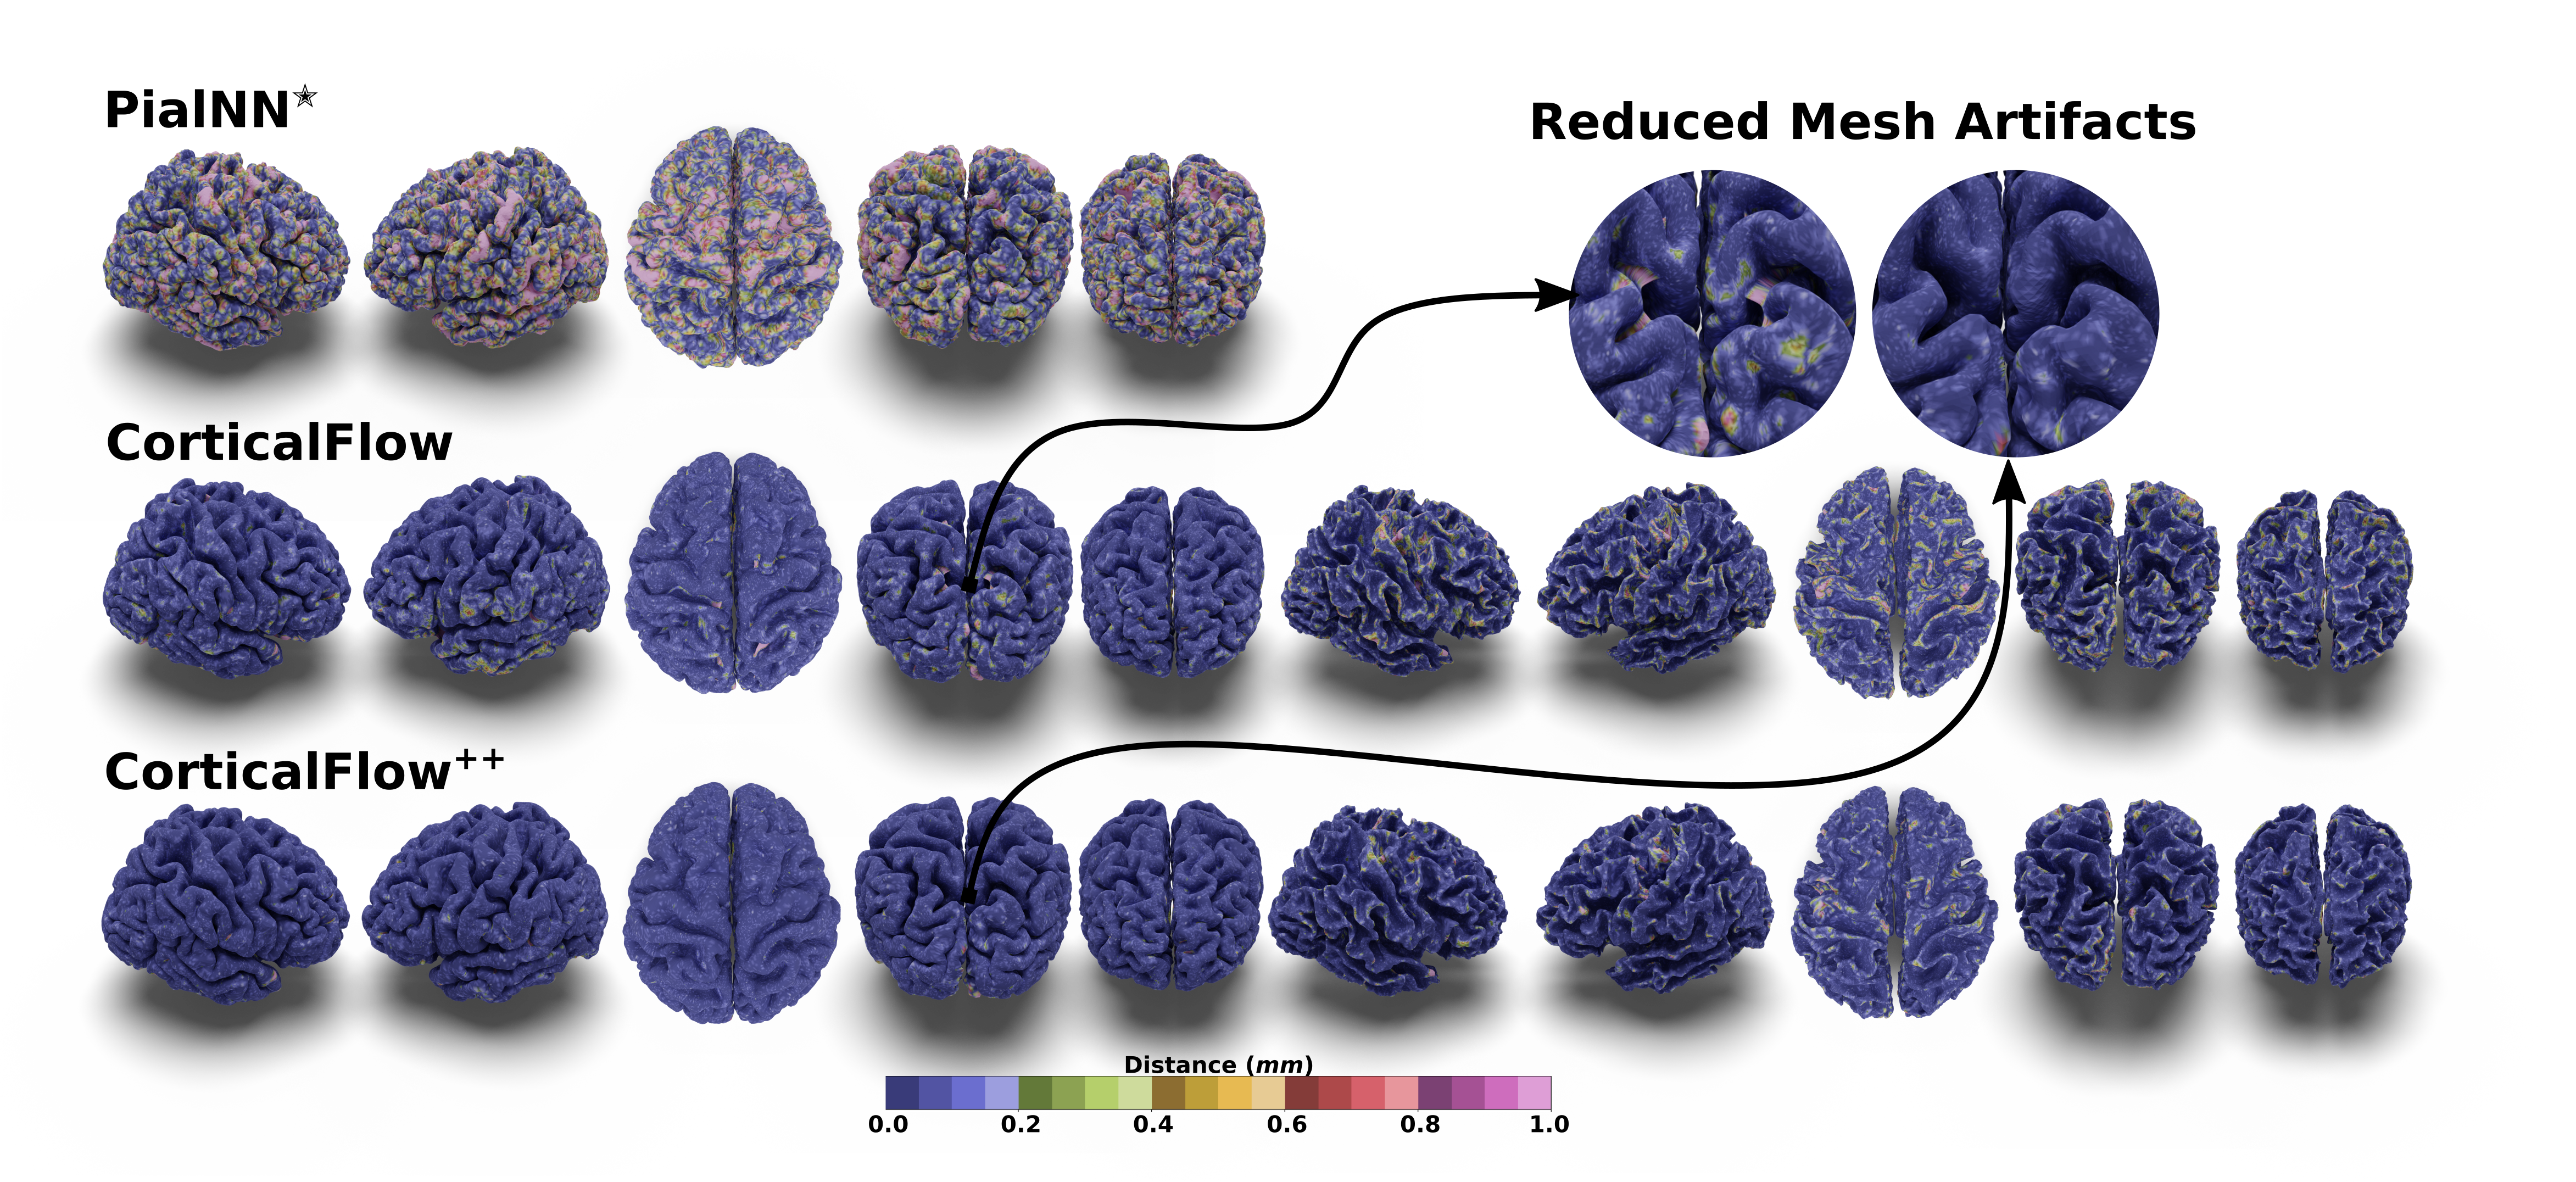

Refer to caption

Figure 3: Predicted cortical surfaces for subject 099_S_0551_m36 in ADNI dataset. The surfaces are color-coded with the distance to the pseudo-ground-truth surfaces.

Figure 4: Predicted cortical surfaces for OASIS3 subjects. The surfaces are color-coded with the distance to the pseudo-ground-truth surfaces.